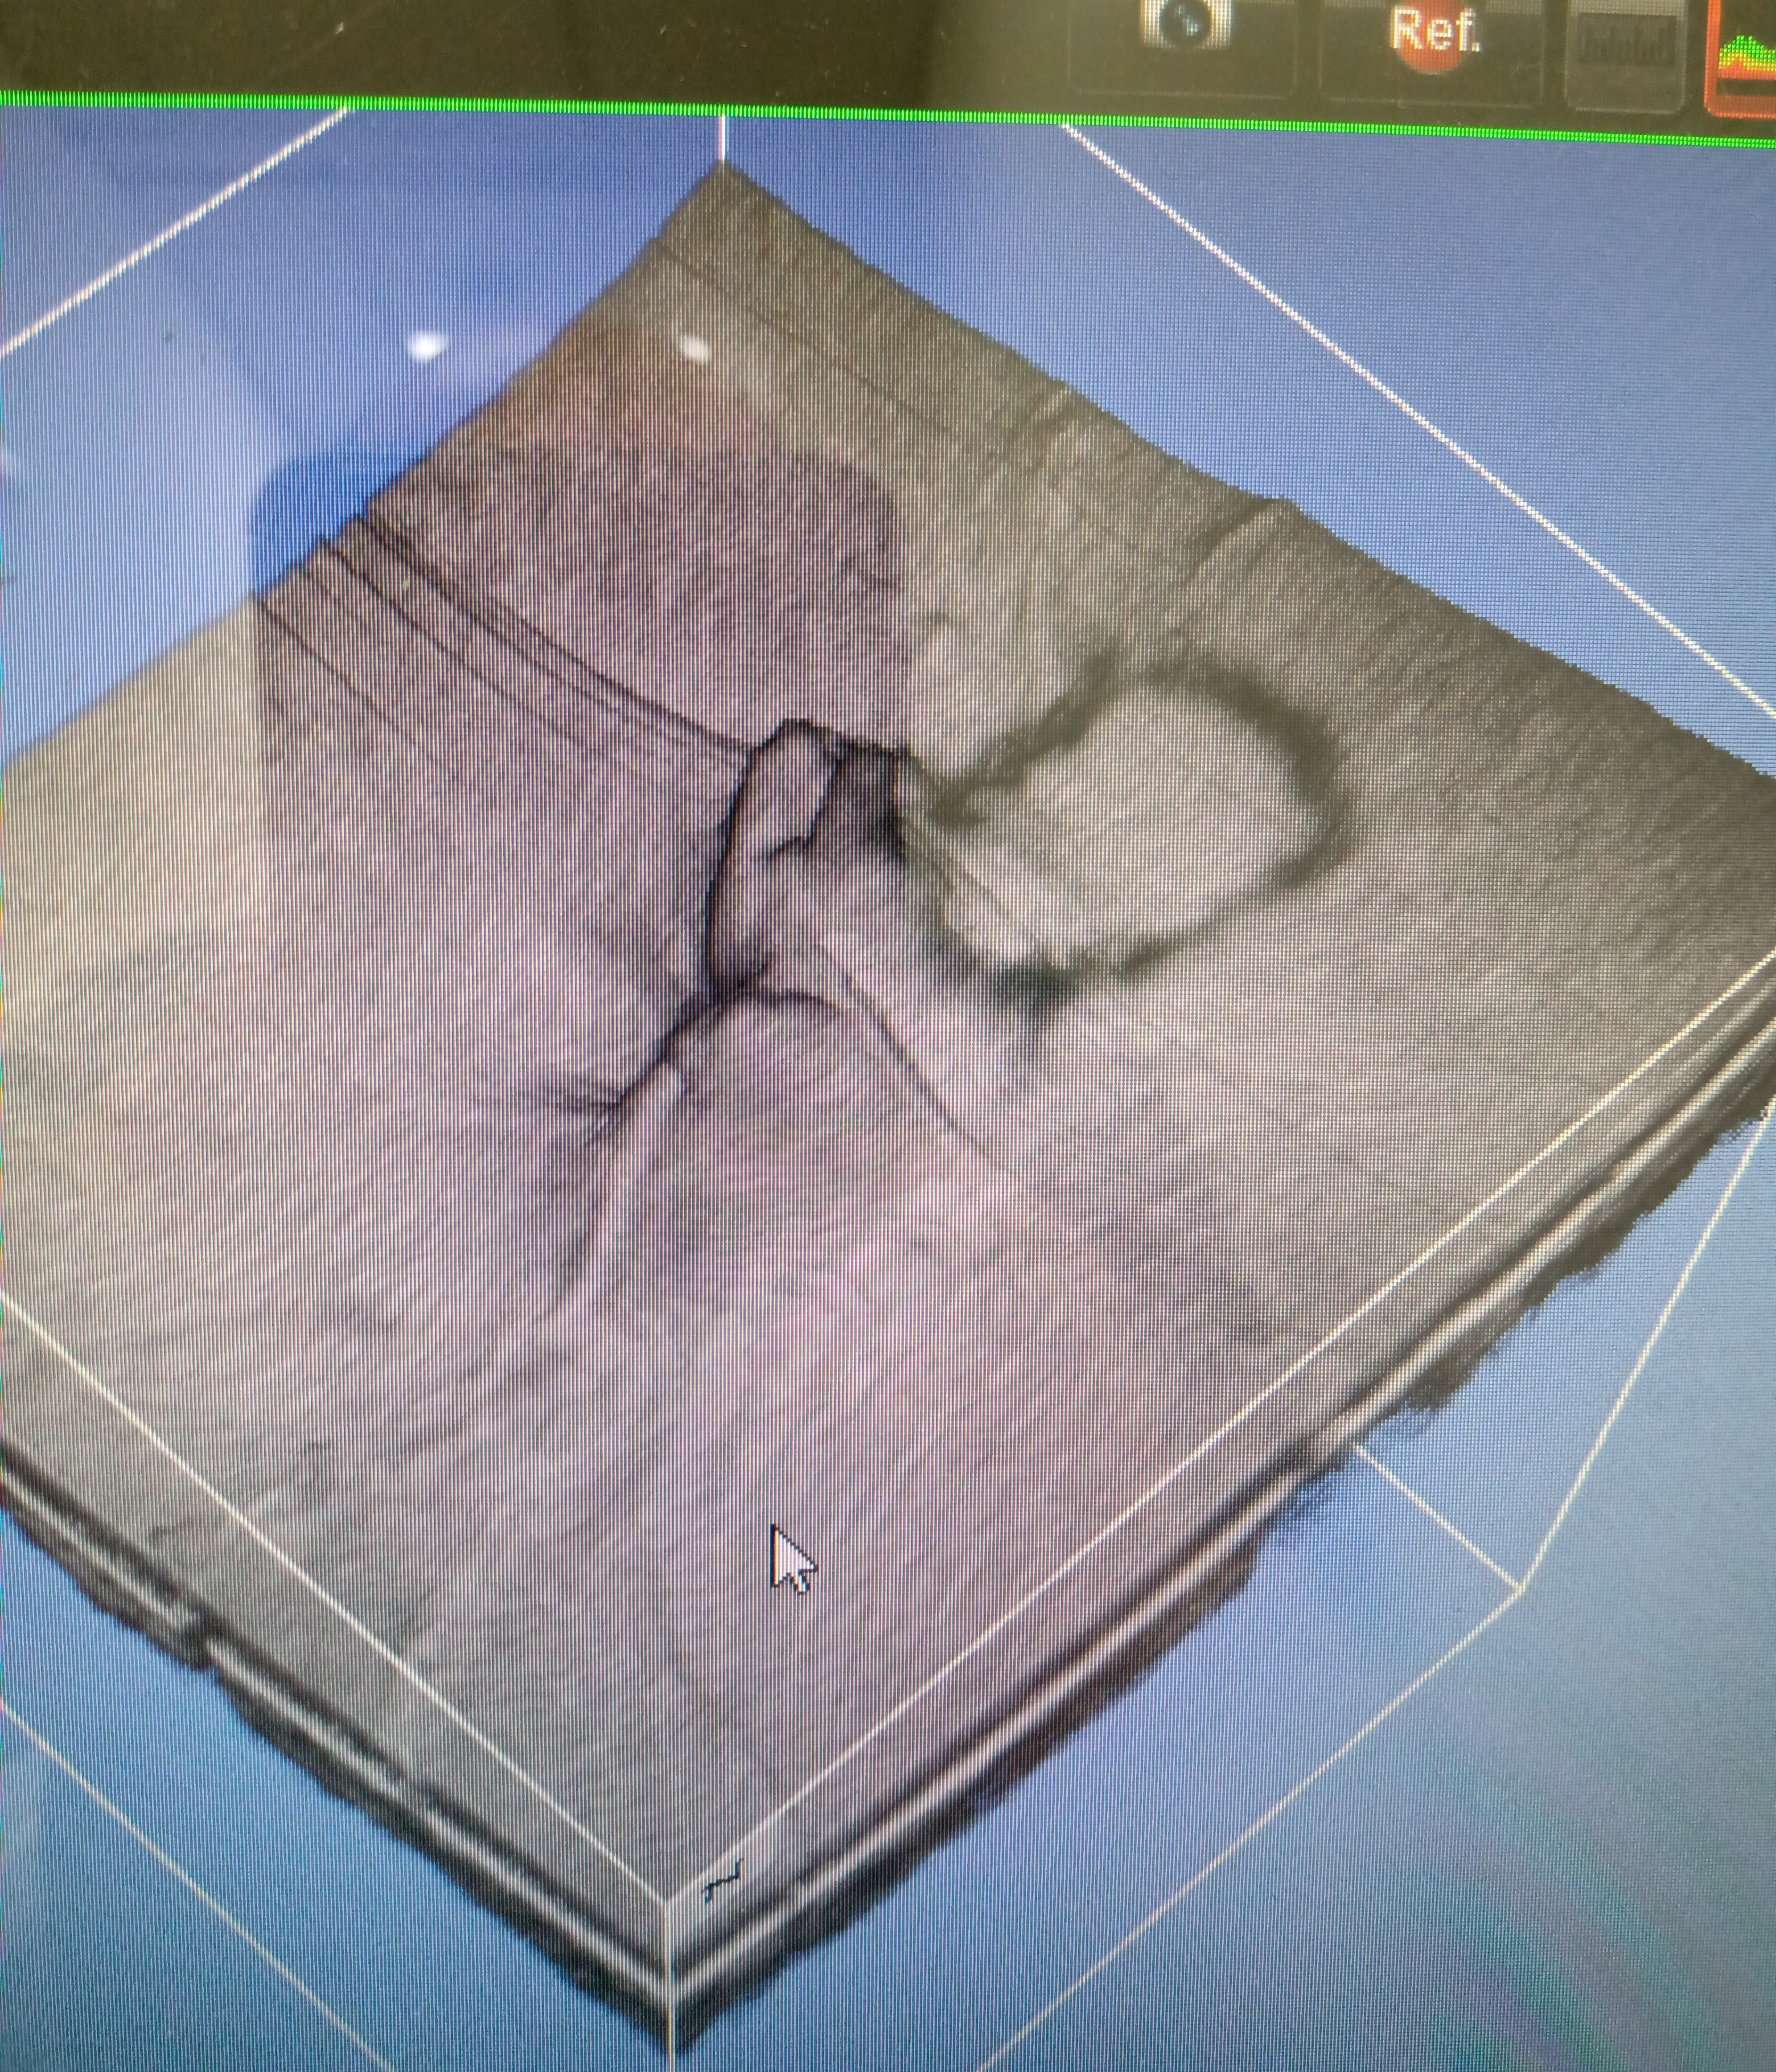

That is a shadow of a floater (Weiss ring) next to a 3D scan of a patient’s optic nerve head which is tilted. All benign but I think it’s really cool

If you say that’s what it is, I’ll believe you. Looks like someone threw a blanket over a baby to me though.

Ohhh that’s super cool, thank you!